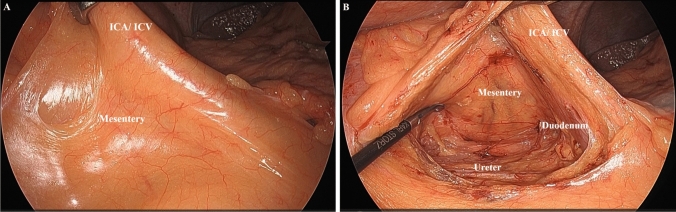

Background: Right-sided colon cancer surgery is a highly difficult operation, and ensuring perioperative safety is an important issue. While various approaches have been proposed for right-sided colon cancer, there are few reports comparing them. The present study compared the inferior approach (IA) and medial approach (MA) for right-sided colon cancer surgery and evaluated their safety.

Methods: We compared 528 cases of right-sided colon cancer surgery performed at our five affiliated institutions from 2017 to 2023, divided into IA and MA groups of 122 cases each using propensity score matching. Short-term outcomes of both groups were retrospectively evaluated, focusing on perioperative complications and perioperative mortality as the primary outcomes.